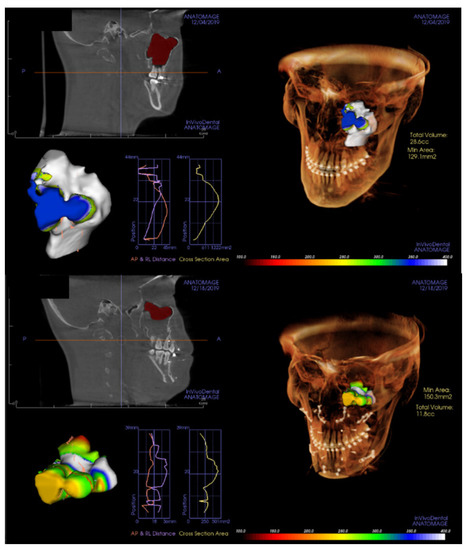

All patients underwent cone-beam computerized tomogram (CBCT, Kavo 3D exam, 37.10 mAs, 120 KVP, acquisition time 17.8 s) before and 2 days after bimaxillary orthognathic surgery. One of the authors analyzed the radiological features using 3D viewer software (Invivo®, Anatomage, San Jose, CA, USA). The middle meatus patency and the ratio of air volume per total maxillary sinus volume were also determined. On coronal view, the patency from the maxillary sinus to the nasal airway was evaluated (Figure 4). The entire maxillary sinus volume before the surgery was analyzed by CBCT using a 3D-volume measuring system for the right and left sides separately. The air volume of the maxillary sinus was evaluated 2 days after surgery with the same method. Further, air volume as per the entire maxillary sinus volume was calculated (Figure 5).

Figure 5.

The entire maxillary sinus volume before the surgery was checked by cone-beam computerized tomogram, using a 3-dimensional volume measuring system (upper). The air volume of maxillary sinus 2 days after surgery was checked with the same method (lower). Then, the ratio of air volume per total maxillary sinus volume (%) was calculated for the left and right sides separately.